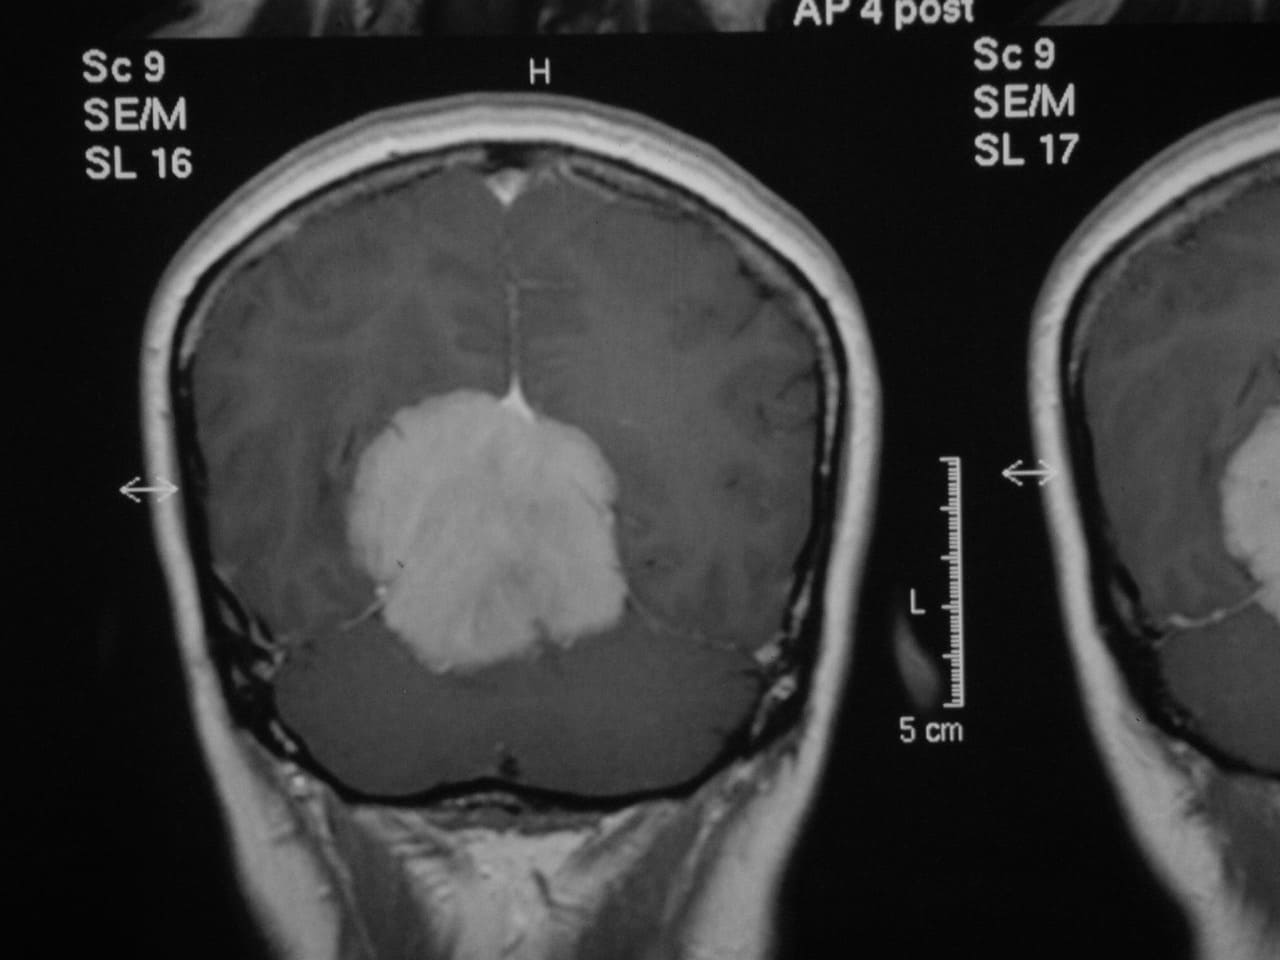

Signos y exámenes

El examen muestra, a menudo, signos neurológicos generales o focales que son específicos del sitio del tumor. Algunos tumores no muestran síntomas hasta que ya son bastante grandes y causan rápido deterioro neurológico, mientras que otros se caracterizan por los síntomas progresivos lentos. La mayoría de los tumores muestra signos típicos de masas que ocupan espacio (lesión ocupante de espacio: LOE), los cuales causan aumento de la presión intracraneal y compresión del tejido cerebral.

El diagnóstico se puede confirmar y el tumor localizar mediante:

• TAC cerebral

• RM cerebral